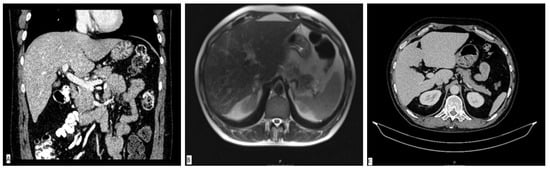

A diagnostic panel excluded acute viral hepatitis as well as metabolic diseases, and the patient denied alcohol consumption or treatment with any concomitant drugs or supplements. An immunology panel revealed positive antinuclear (ANA), anti-mitochondrial (AMA) and AMA-M2 antibodies with increased immunoglobulin G (IgG) levels. Other autoimmune antibodies were negative. Liver sonography and an abdominal MSCT scan were ordinary (Figure 2A). He was treated with corticosteroid therapy (prednisone 1 mg/kg/day) and ursodeoxycholic acid (UDCA, 13 mg/kg/day), which led to a significant decrease in laboratory parameters. The calculated Roussel Uclaf Causality Assessment Method (RUCAM) score was 5, indicating the possible causality of the aforementioned supplement.

The patient was perceived as having hepatocellular DILI and further treated as an out-hospital patient with tapering doses of corticosteroid therapy. In June 2017, three months after admission, corticosteroid therapy was withdrawn due to the complete normalization of laboratory parameters. In September 2017, an increase in aminotransferase levels was detected and the corticosteroid therapy was initiated again. In October 2017, liver MR was performed and described a rough structure of the right liver lobe, more pronounced in the peripheral zones, where coarser thickened septa with initial retraction of the liver parenchyma were observed, suggesting initial cirrhotic changes (Figure 2B). In December 2017, he was admitted again due to a significant increase in aminotransferase and bilirubin levels. A biopsy of the right liver lobe was performed, showing abundant T lymphocyte and plasma cell infiltration with numerous areas of piecemeal necrosis, without cholestasis. This finding corresponded with chronic active hepatitis, morphologically dominantly autoimmune hepatitis of medium activity (modified hepatitis activity index (mHAI) according to Scheuer 8–9/18) with liver fibrosis (stage 2/6) (Figure 3). After increasing the corticosteroid dose, a decrease in laboratory parameters was detected. He was further treated as an ambulatory patient with tapering corticosteroid doses and UDCA. The patient remained under biochemical control under low-dose corticosteroid therapy (prednisone 5–10 mg/day), with no further relapses.

In March 2019, two years after the initial admission, a control abdominal MSCT scan was performed and showed an atrophic right liver lobe with irregular contours and a hypertrophic left lobe, indicating the presence of liver cirrhosis (Figure 2C). Since the left liver lobe seemed spared of fibrotic changes, it was biopsied and revealed insignificant inflammatory infiltrate without piecemeal necrosis, cholestasis or advanced fibrosis.

Figure 2. Radiological imaging of the liver parenchyma. MSCT scan of liver performed in March 2017 showing normal liver parenchyma (A). MR scan of liver performed in October 2017 showing a rough structure of the right liver lobe with initial retraction of the liver parenchyma, suggesting initial cirrhotic changes (B). Liver CT scan from March 2019 demonstrating liver cirrhosis (C).